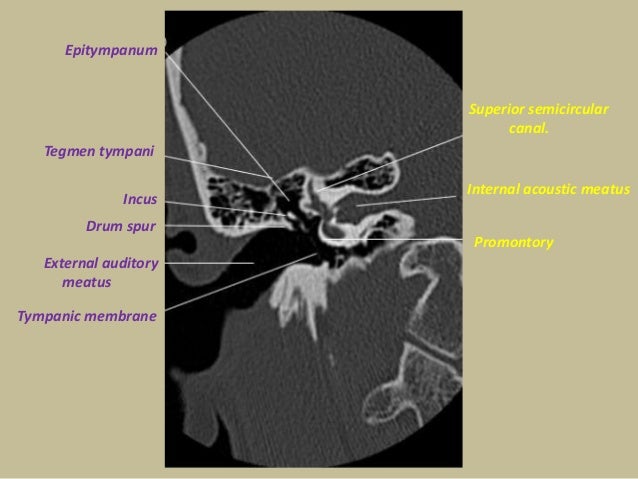

Presentation1.pptx, Radiological Anatomy Of The Petrous Bone.

Presentation1.pptx, radiological anatomy of the petrous bone. www.slideshare.net

petrous radiological tegmen tympani presentation1 epitympanum pptx